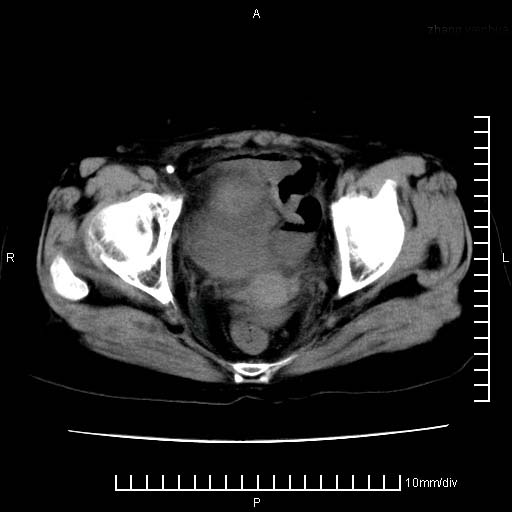

下腹疼痛2月,加重并呕吐2天,下腹压痛,反跳痛。白细胞1万2.

下腹至盆腔较大包块,与邻近肠管关系密切,下腹疼痛2月,加重并呕吐2天,下腹压痛,反跳痛。白细胞1万2.

支持楼上意见:考虑回盲部慢性炎症,并包裹积脓肿。

盆腔脓肿伴盆腔积液

不知道大家可要注意下腹腔小肠旁不规则结节状灶,部分钙化,是否要考虑小肠腺癌.盆腔包块可能考虑脓肿.

考虑卵巢恶性肿瘤;盆腔积液。